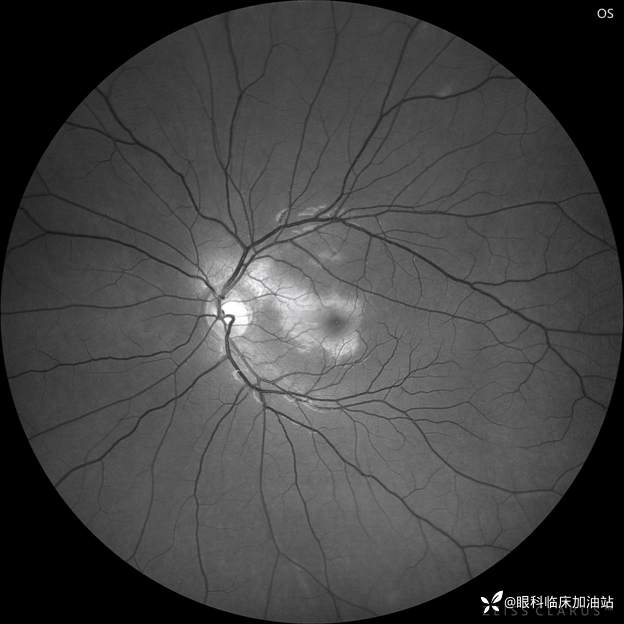

眼底照相

局部细节图

无赤光眼底照相